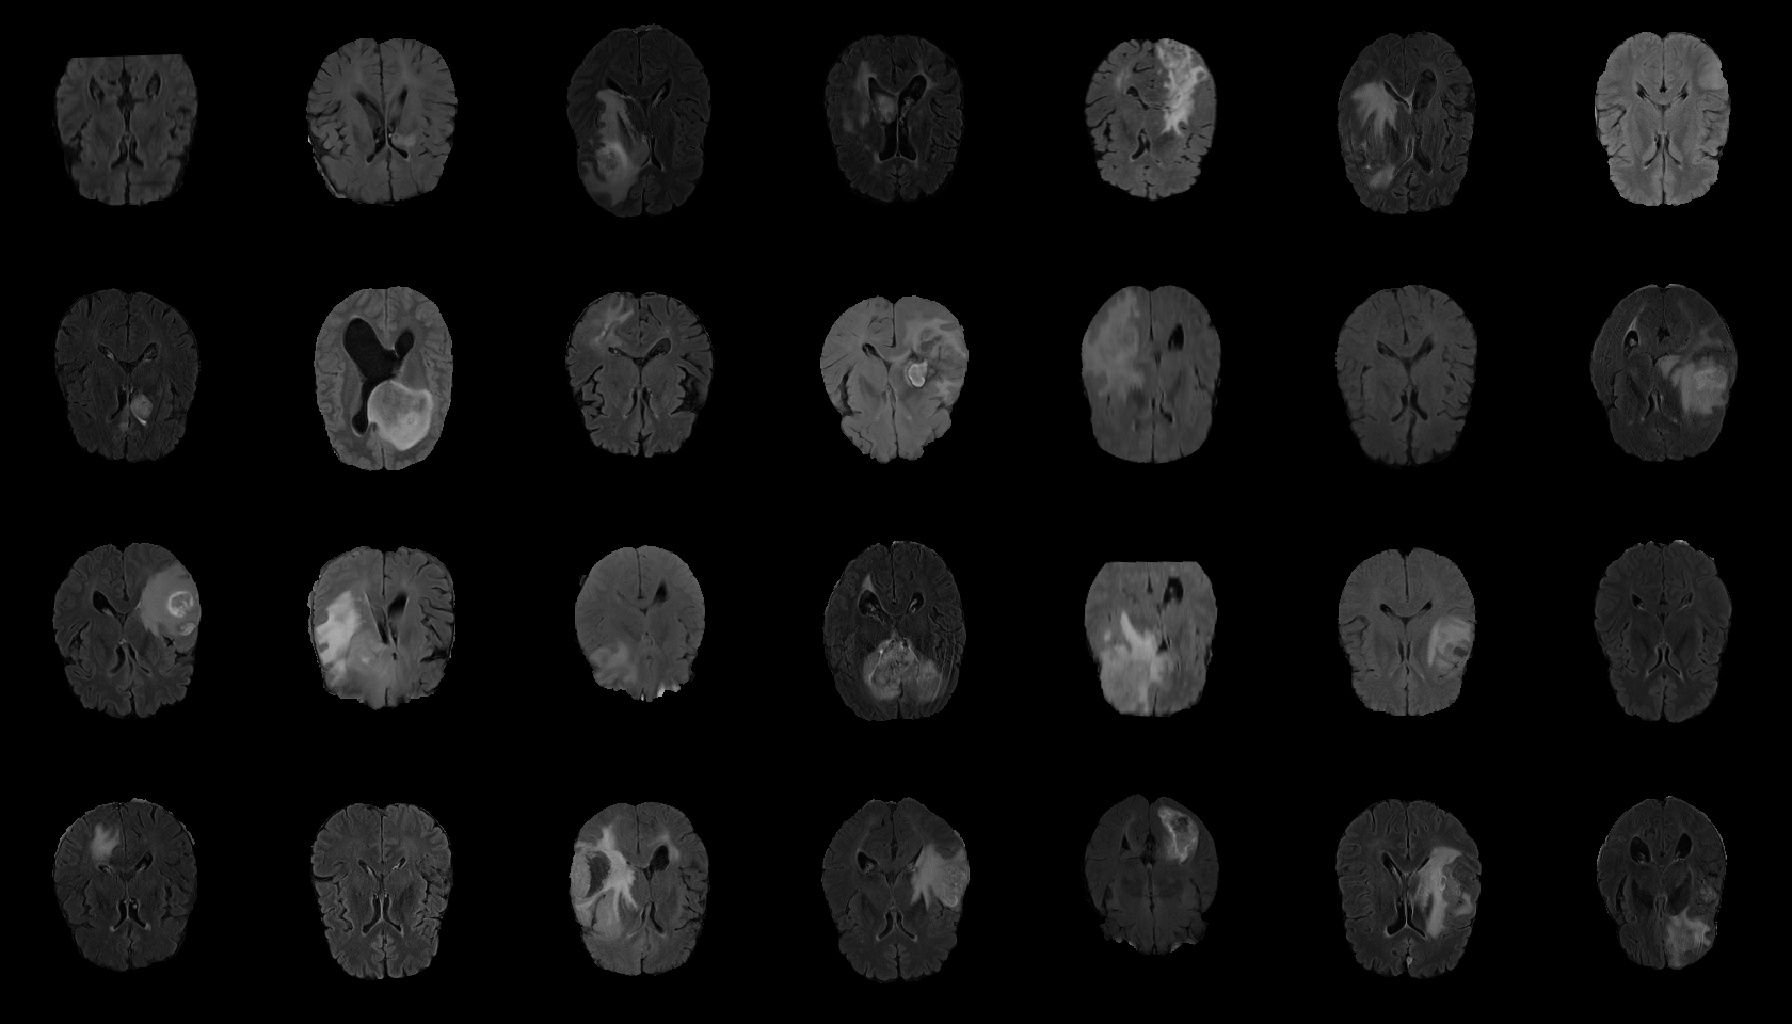

This research exploits the BRATS 2019 training dataset containing 259 High-Grade Gliomas (HGG) cases. We select the 64th slice among the whole 155 slices as the initial/final slices will convey a negligible amount of information and affect the training [32]. Therefore, the training dataset is 259 FLAIR brain axial (AXI) MR images, zero-padded to 256 x 256 from original-sized 240 x 240 pixels for better GAN training. Figure 4 shows real FLAIR samples.

Generated Images Figure 5 shows the generated brain tumor FLAIR samples from -GAN-GP, PGGAN, and PGGAN-SSIM in AXI. The generated samples from all models look realistic and are close to the real images, where the white areas (Gliomas area) are concentrated and unified, indicating the training stability with gradient penalty. However, the samples from -GAN-GP are blurry, and the detailed brain features disappear since the loss of image information becomes serious when the image resolution increases in -GAN-GP. The generated samples from PGGAN and PGGAN-SSIM have clear and realistic brain features (FLAIR texture and tumor appearance) with diversity, which illustrates that PGGAN architecture is a well-suited model to generate brain MR images.